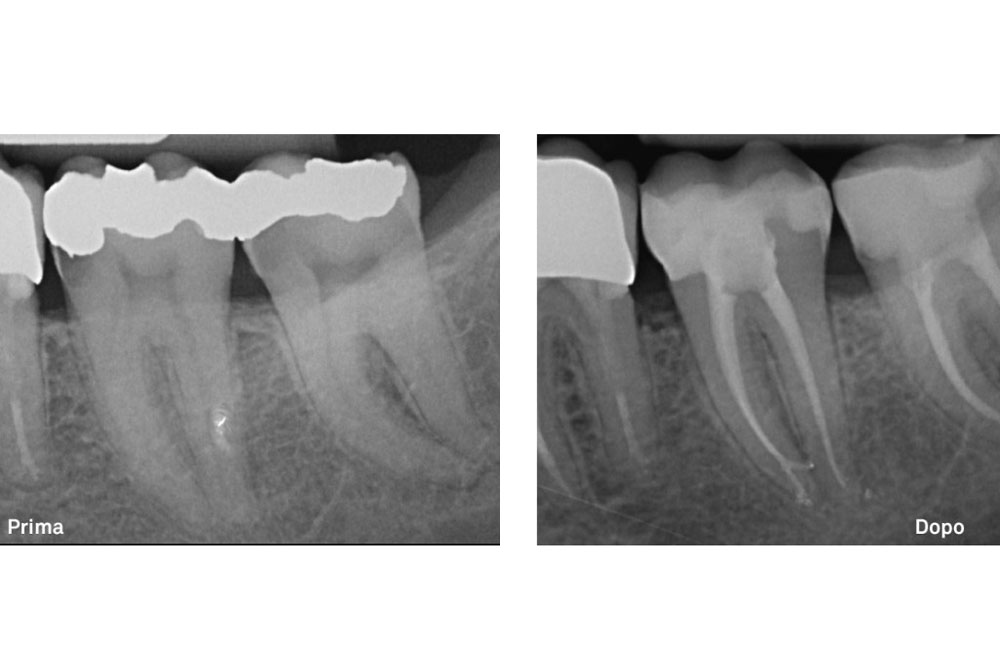

Si ricorre alla terapia endodontica qualora una lesione cariosa o traumatica al dente abbia determinato una alterazione irreversibile del tessuto pulpare, fino alla necrosi dello stesso. È possibile inoltre ricorrere a questa metodica qualora l’elemento dentario debba essere coinvolto in riabilitazioni protesiche che, a causa della notevole riduzione di tessuto dentale stesso, determinerebbero con alta probabilità un’alterazione pulpare irreversibile (necrosi pulpare per cause iatrogene).